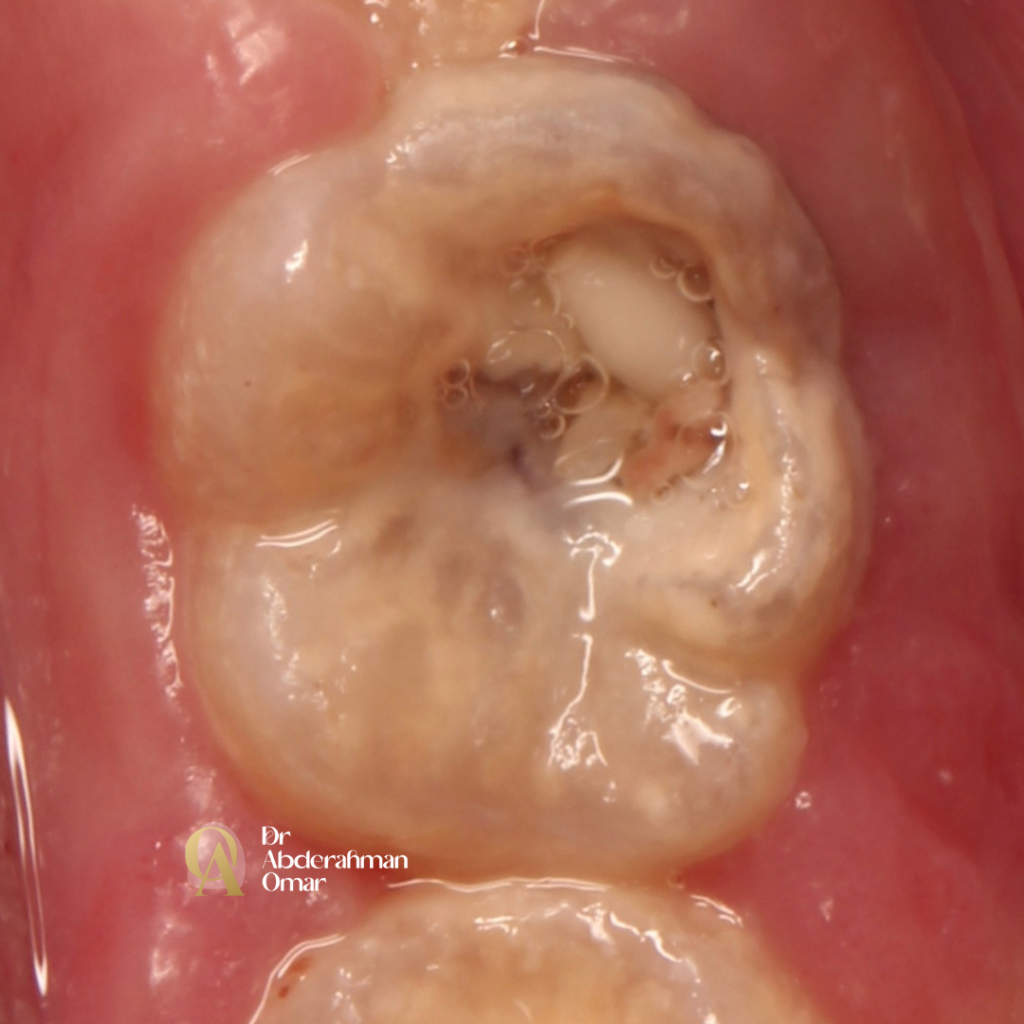

Today’s case involves a 13-year-old patient presenting with symptomatic irreversible pulpitis in the mandibular left first molar. Clinical examination revealed deep caries with positive tenderness to percussion and thermal sensitivity.

Upon access cavity preparation, careful exploration under magnification confirmed an atypical and complex canal anatomy: 5 distinct canals — 3 mesial canals (MB, MM, ML) and a Type III distal canal configuration (1 orifice dividing into 2 canals).